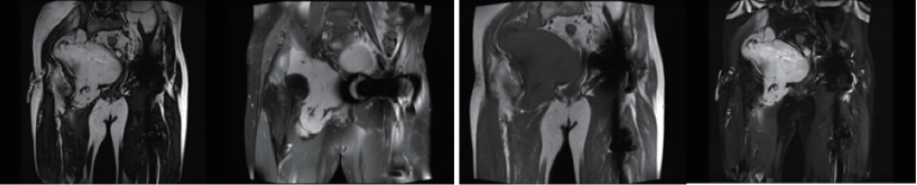

案例圖

骨與軟組織腫瘤